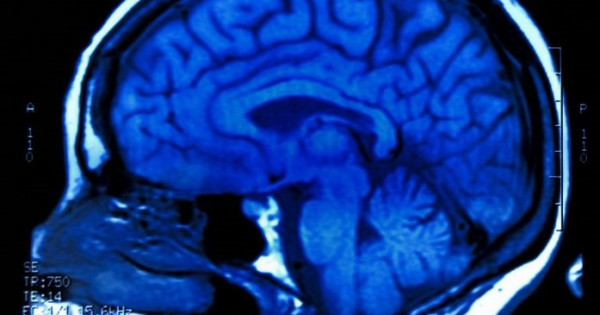

Ǵalymdar adam mıynyń qury­lymyna qatysty tańǵalarlyq jańalyq ashyp, buryn bel­gisiz bolyp kelgen juqa qabatty anyq­tady.

Ǵalam ǵajaptary: Mıdyń jańa qabaty

Bul qabat mıdyń syrtqy qyrtysy men ishki qurylymdary arasynda orna­lasqan jáne onyń neırondyq baılanys­tardy retteýge qatysatyny baıqalǵan. Zertteýshiler bul jańalyqtyń alsgeımer, parkınson sııaqty nevrologııa­­lyq ­aýrýlardy emdeýde jańa múmkindik ­tý­ǵyzýy ǵajap emes.